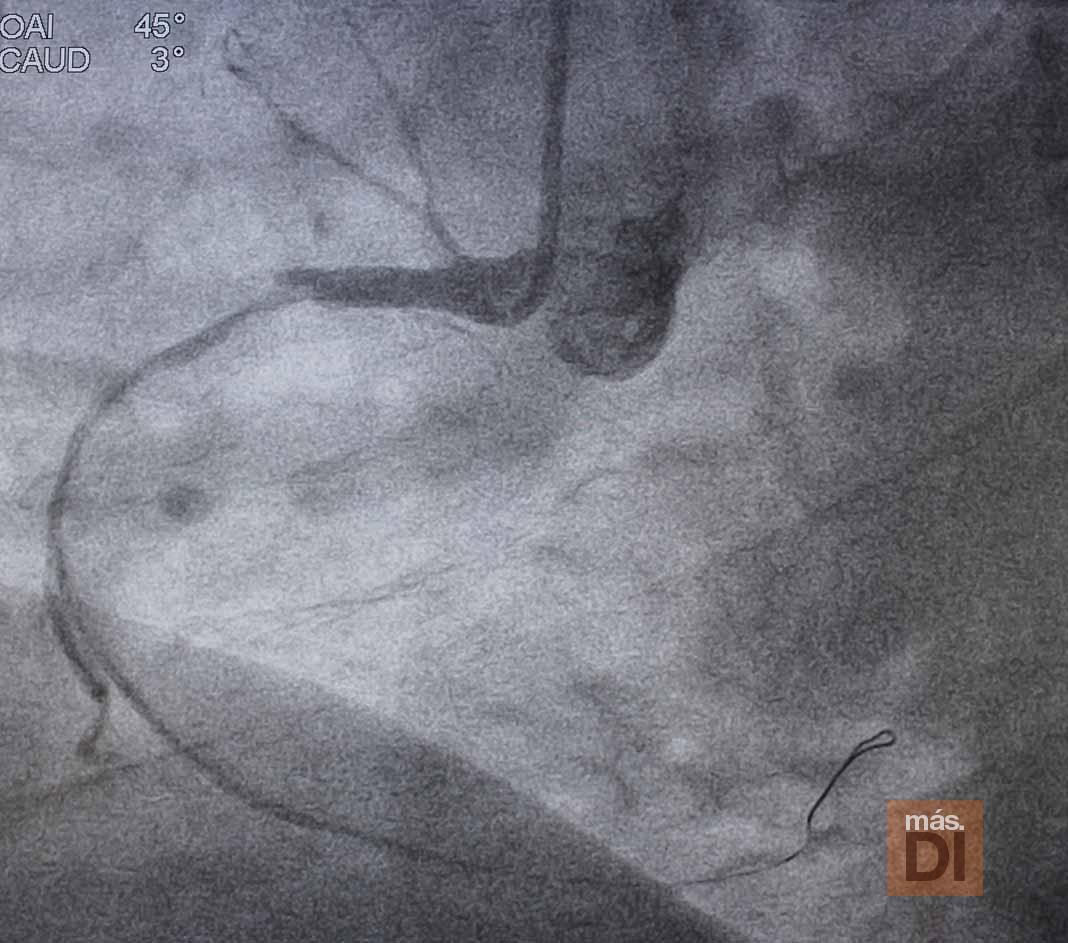

Una vez llega la ambulancia a la Policlínica, el paciente es trasladado directamente a la sala de hemodinámica, donde se le realiza el cateterismo cardíaco que finalmente logrará la apertura del vaso responsable del infarto en un plazo de 20-30 minutos y, según el caso, se implantará un stent coronario (un pequeño tubo de malla de metal) que mantendrá la arteria abierta.

Los estándares europeos establecen como meta lograr la apertura del vaso tras el primer contacto médico, en un plazo de menos de 60-90 minutos, según requiera o no traslado de ambulancia, estándares que el Código Infarto implantado en Ibiza cumple. Esto pone en relieve la calidad asistencial que se presta en la isla, igualando a las grandes ciudades de España y Europa.